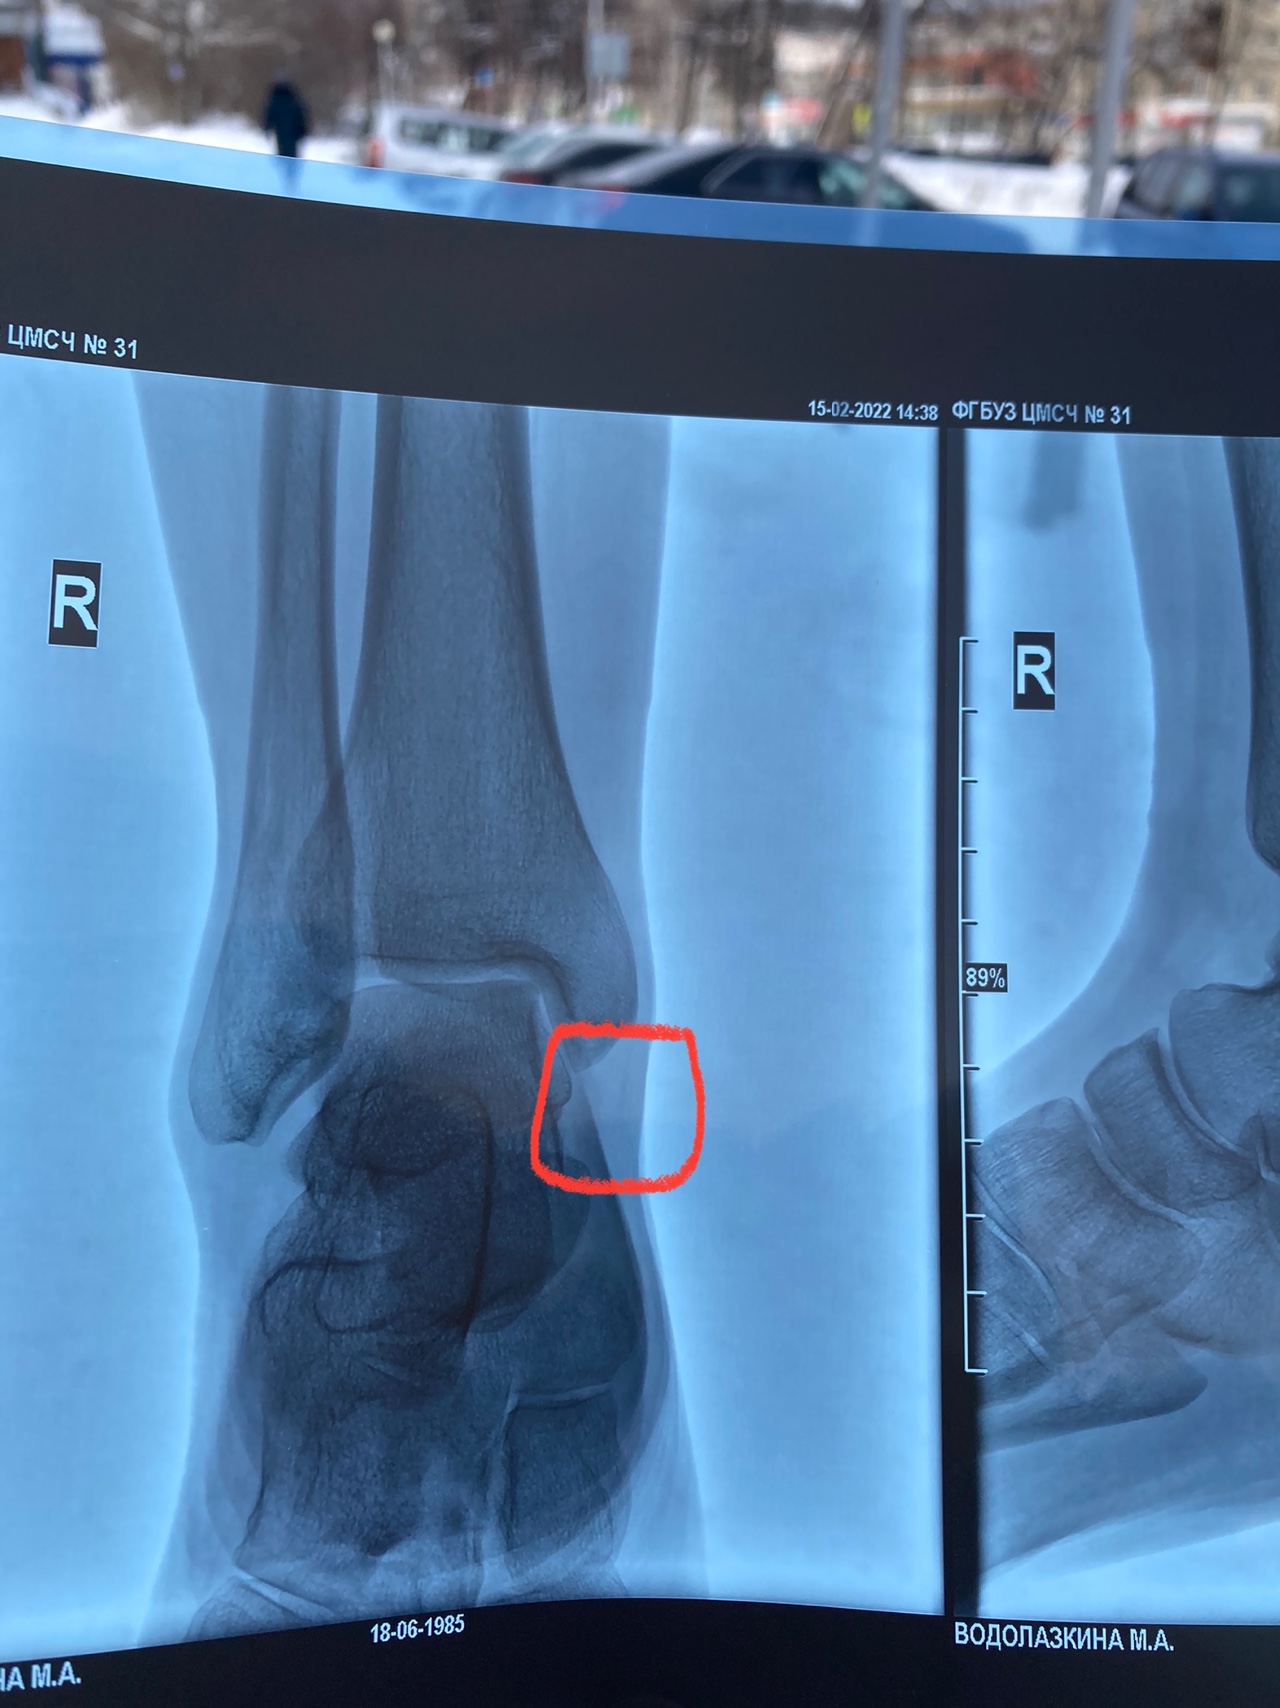

Рентгеновские технологии: усиленные экраны 35x35